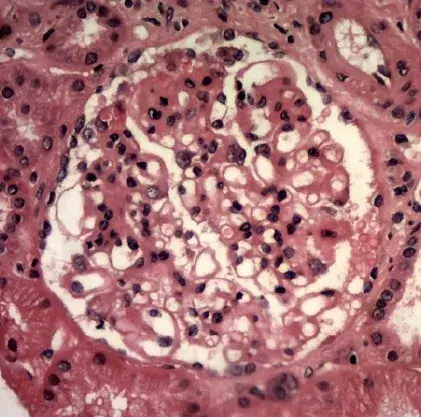

A imunofluorescência mostra marcação linear de IgG na MBG (anticorpo anti-IgG; 400×).

A imunofluorescência demonstrou padrão de deposição linear de IgG (policlonal), deposição na membrana basal glomerular (MBG), sem depósitos na microscopia eletrônica.